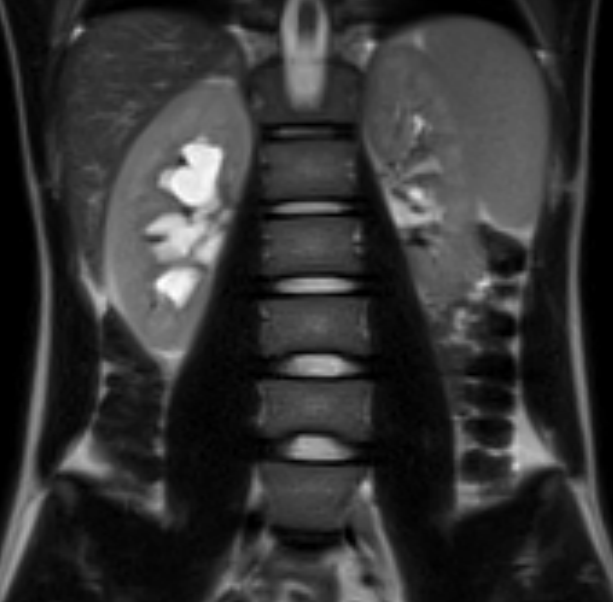

Магнитно-резонансная томография мочевыделительной системы – важный метод исследования, который позволяет оценить состояние почек, надпочечников и мочевыводящих путей.

• МРТ почек и надпочечников

• МРТ мочевыделительной системы с бесконтрастной урографией